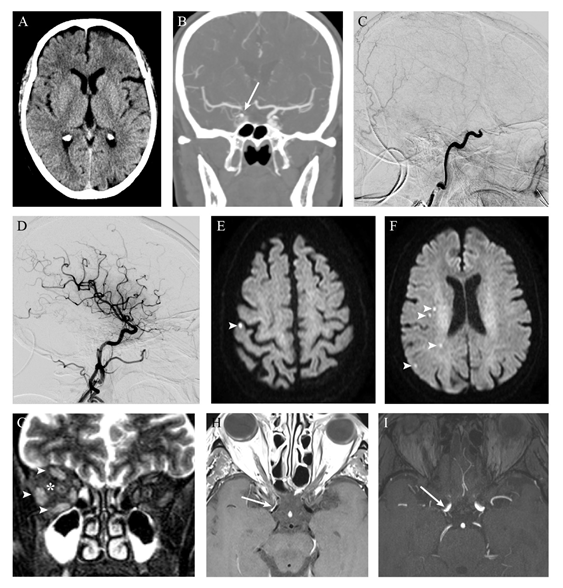

On admission, she had no neurological deficits (National Institutes of Health Stroke Scale (NIHSS) 0). Head computed tomography (CT) showed no signs of intracranial bleeding or acute ischemia (Alberta Stroke Programme Early CT Score (ASPECTS) 10) (Figure 1A). CT angiogram (CTA) showed an acute right distal internal carotid artery (ICA) occlusion, without other significant occlusions or stenosis (Figure 1B). Our stroke team was contacted at this moment and the patient was transferred to our hospital, to proceed with MT, where she arrived nine hours after symptoms onset. Her NIHSS score was still 0. Her systolic blood pressure fluctuated between 170 and 200 mmHg and diastolic blood pressure ranged from 65 to 85 mmHg.

Following right femoral artery punction an 8F artery short sheath was placed. The right common carotid artery was then catheterized using a Neuron Max and a 6F Simmons II catheters. The first angiographic run confirmed an occlusion at the cavernous segment of the right ICA (Figure 1C). The clot was removed after a single pass with combined technique (using a 6,5 x 45 mm stentretriever and distal aspiration). After clot removal, a residual right M1 stenosis was seen. The final modified Thrombolysis in Cerebral Ischemia was 3 (Figure 1D). The femoral access was closed with a 6F Angio-Seal vascular closure device. At the end of the procedure, she had a normal neurological examination (NIHSS 0) and no orbital involvement was noticed. In the following hours, the systolic blood pressure ranged from 90 and 110 mmHg and the diastolic blood pressure between 45 and 55 mmHg.

Eight hours later, she complained of right orbital pain. Ptosis, chemosis and complete ophthalmoplegia of the right eye were observed (Figure 2 A-D). Visual acuity and funduscopic examination were normal and there was no audible bruit in the orbit. A repeat CT did not show any acute ischemic or hemorrhagic lesions. CTA showed a slight enlargement of the right medial and lateral rectus muscles. To rule out a possible carotid-cavernous fistula (CCF), cerebral angiography was performed and was negative for complications or fistulae. Steroid treatment ensued with IV dexamethasone (8 mg, three times a day). Brain MRI performed forty-eight hours after symptoms onset showed punctuate acute ischemic lesions in the right hemisphere (Figure 1E&F). Coronal T2 with fat saturation showed hyperintensity of orbital fat along with hyperintensity and enlargement of all extraocular muscles (Figure 1G). There were no signs of orbital infarction or cavernous sinus thrombosis. Optic nerve was structurally normal. Time of flight magnetic resonance angiography revealed calibre reduction of the distal portion of ICA (Figure 1I), with corresponding contrast enhancement on vessel wall imaging (Figure 1H).

Figure 1 Radiologic findings. Early non-contrast CT excluded intracranial hemorrhage and showed no features of acute ischemia (A) A contrast filling defect on the terminal right internal carotid artery (arrow) was revealed on CT angiography. Digital subtraction angiography demonstrated occlusion of the right internal carotid artery at the cavernous segment (C) After mechanical thrombectomy, complete recanalization was obtained, with no signs of complications (namely carotid-cavernous fistula) (D) Brain MRI performed two days later showed only scarce foci of restricted diffusion (arrowheads) on DWI images (E-F), with corresponding low signal on apparent diffusion coefficient map (not shown), reflecting ischemic lesions on the vascular territory of right internal carotid artery. Coronal T2 fat satured images revealed right orbital inflammatory features manifested by faint hyperintensity of orbital fat (*) and extraocular muscles enlargement with hyperintensity (arrowheads) (G) Vessel wall imaging after contrast administration showed eccentric enhancement of the anterior wall of distal internal carotid artery on the right (arrow, H), where luminal stenosis was found on time-of-flight angiography (I).